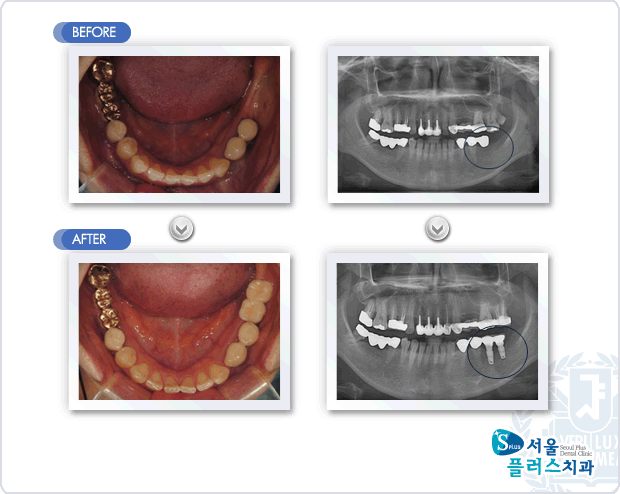

[임플란트] 하악 좌측의 치아 상실과 오래된 보철물